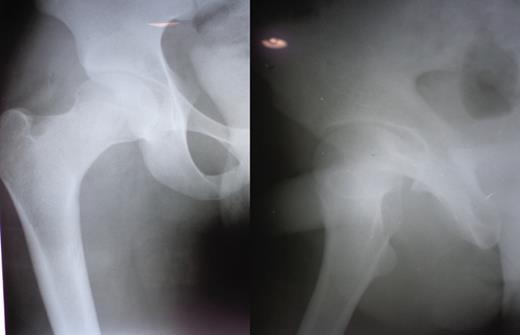

A 23-year-old male pavement dweller was brought to the emergency department of this hospital after being hit by a tempo. The patient was in a state of shock with an open right-sided anterior hip dislocation with the femoral head being visible in the inguinal region (Fig. 1). The neurovascular status of the right lower limb was intact. Immediate resuscitation was done and hip radiographs (Fig. 1) were taken, which showed an anterior-inferior dislocation with an inferior pubic ramus fracture on the left side. The patient was immediately transferred to the operating room where the wound was thoroughly debrided and the femoral head was relocated within 5 hours of sustaining the trauma (Fig. 2). The wound after surgical debridement was 8 × 6 cm in dimensions, which was primarily closed after checking for the stability of the reduction. The patient was started on intravenous metronidazole, amikacin and ceftriaxone for 5 days, followed by oral amoxicillin for a week. The patient was kept non-weight-bearing on skin traction for 6 weeks. The wound healed satisfactorily with no evidence of infection, nor any episode of re-dislocation at 6 months (Fig. 3). The patient was unfortunately lost to follow-up.

Figure and radiograph showing an open anterior hip dislocation.